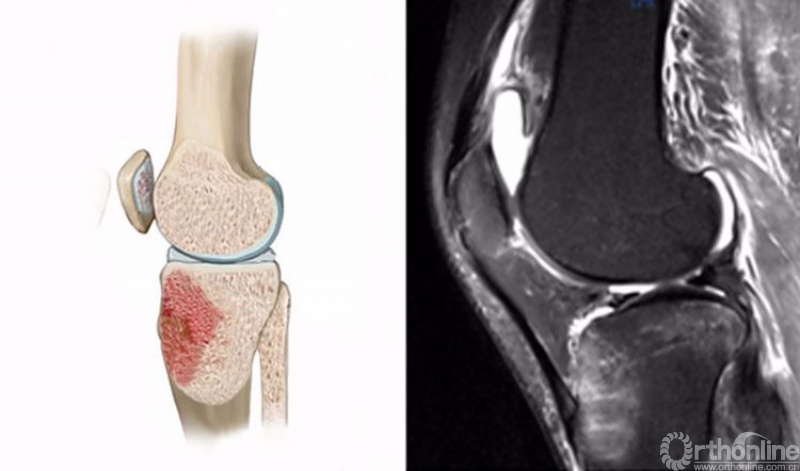

2.仪表板损伤(dashboard injury)

膝关节屈曲时,外力作用于胫骨近端前方,多见于车祸时膝关节撞击前方的仪表盘,也见于跌倒时膝关节撞击地面,是后交叉韧带(PCL)最常见的损伤机制。

膝关节仪表板损伤在MRI上主要表现为胫骨上端前方的骨髓水肿,T2WI及STIR像呈高信号改变,一般预示着PCL损伤。